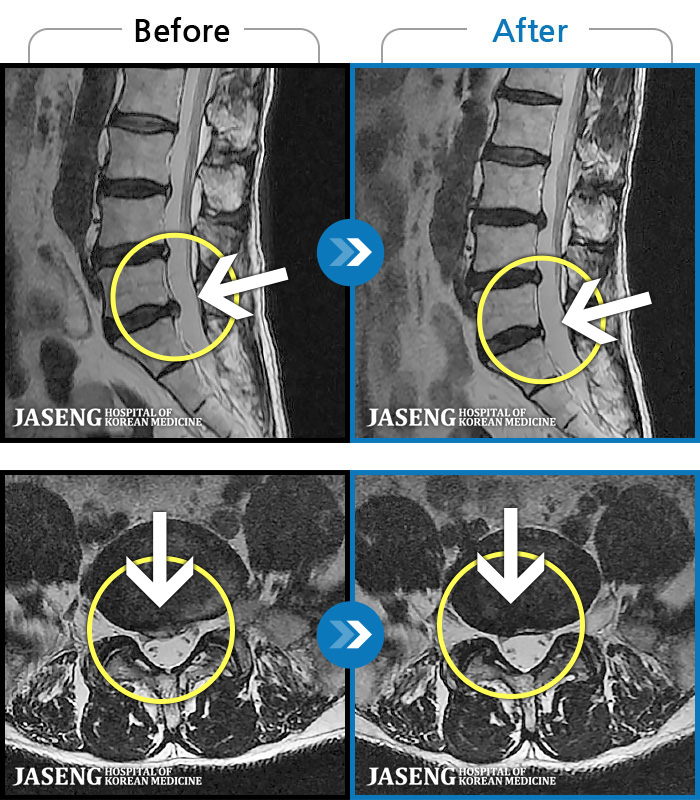

- MRI ġ

MRI ġ

1,240 MRI ũ ʸ Ȯϼ.